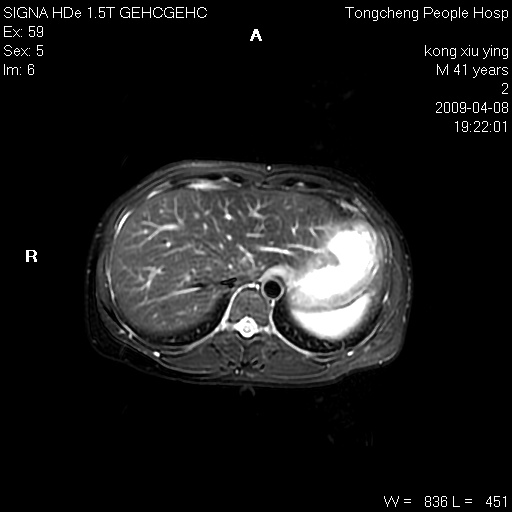

标题: CL1008:【经典】胆囊石榴籽样结石。 [打印本页]

标题: CL1008:【经典】胆囊石榴籽样结石。

女,41岁。健康体检——彩超提示:胆囊显示不清。平素健康,无不适感。

腹部mr扫描及mrcp,图像如下:

石榴籽样阴性结石,学习了!

胆囊石榴籽样结石。